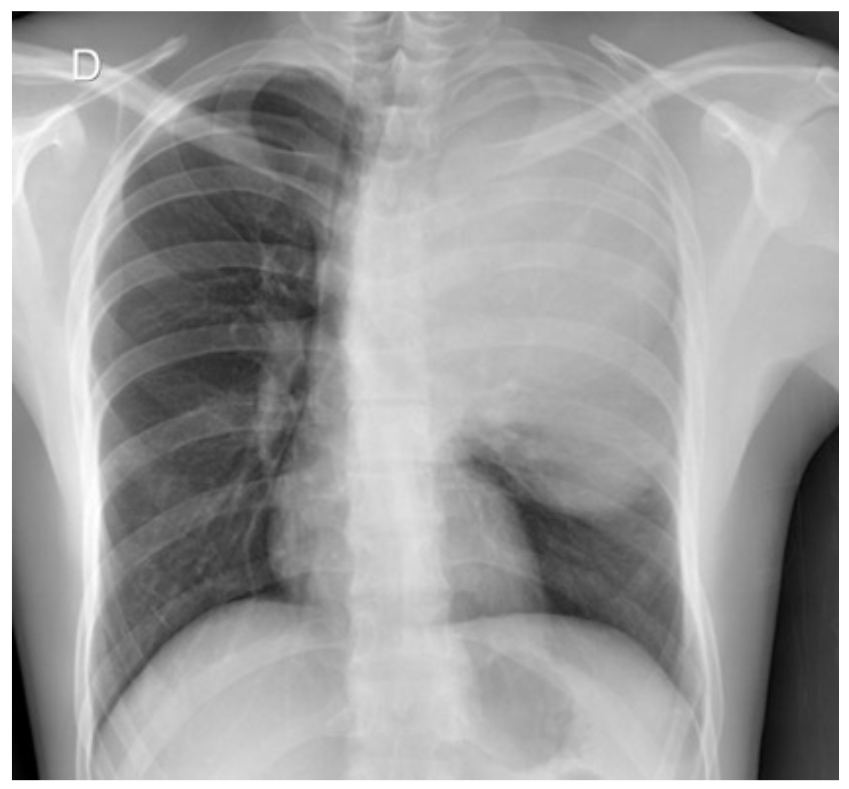

El caso corresponde a un hombre de 38 años de edad, sin antecedentes de importancia, cuyo padecimiento inició dos meses antes, con astenia, adinamia y fatiga, que dificultaba actividades de la vida cotidiana, además de tos seca y disnea de grandes esfuerzos. Acudió a atención médica y se le indicó tratamiento sintomático, pero no hubo mejoría. Diez días después, tuvo tos en accesos y la disnea se fue incrementando progresivamente hasta incluso aparecer en reposo. Se le indicó manejo sintomático, pero tampoco mejoró el cuadro clínico. Se le solicitó, entonces una radiografía de tórax, en la cual se observó una lesión pulmonar ocupativa en lóbulo superior izquierdo (figura 1).

Figura 1. Radiografía posteroanterior de tórax que muestra una lesión pulmonar en el lóbulo superior izquierdo, radiopaca, con aspecto sólido, bordes bien definidos, con efecto masa sobre la tráquea, bronquios y grandes vasos que se desplazan en sentido contralateral, con un tamaño aproximado de 16 x 10 cm en sus ejes longitudinal y transverso